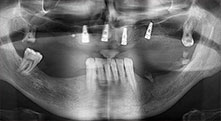

Bratu: Wir augmentieren im seitlichen Unterkiefer gern mit der Sandwich-Technik. Dabei wird ein Knochendeckel mit der Piezosäge präpariert und das krestale Fragment mit Mikroschrauben fixiert. Dazwischen platzieren wir eine Mischung aus autologem Knochen und xenogenem Knochenersatzmaterial. Das funktioniert sehr zuverlässig. Bei Kieferkammspaltungen im Unterkiefer sollten Sie nie auf ausreichend dimensionierte vertikale Schnitte verzichten. Sonst kann der Knochen leicht frakturieren.